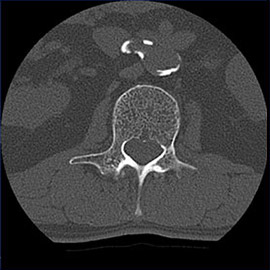

80列マルチスライスCTで撮影した画像

腹部

腹部(造影)

体脂肪計測

1スライスの腹部単純撮影画像から体脂肪面積や皮下脂肪面積を計測し、それぞれの蓄積を観察できます。